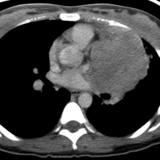

Thymic carcinoma CT

Date: 08/15/2012

Views: 5971